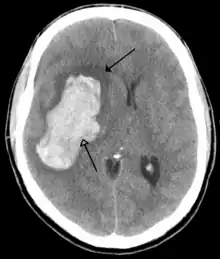

CT scan of an intraparenchymal bleed (bottom arrow) with surrounding edema (top arrow)

There are two main types of hemorrhagic stroke:[28][29]

Hemorrhagic strokes may occur on the background of alterations to the blood vessels in the brain, such as cerebral amyloid angiopathy, cerebral arteriovenous malformation and an intracranial aneurysm, which can cause intraparenchymal or subarachnoid hemorrhage.